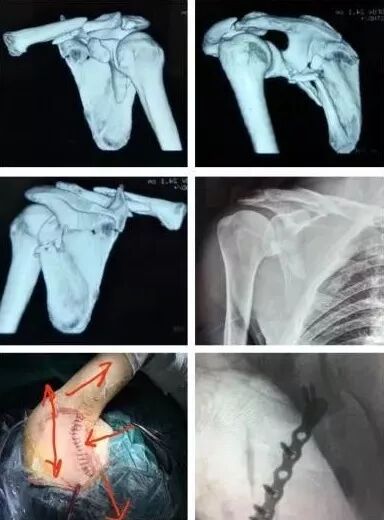

(2)肩胛带骨折

1)锁骨骨折

图片

骨折伤及锁骨下动脉,臂丛,应立即手术。

2)肩胛骨骨折

在2周之后手术,困难程度翻番。